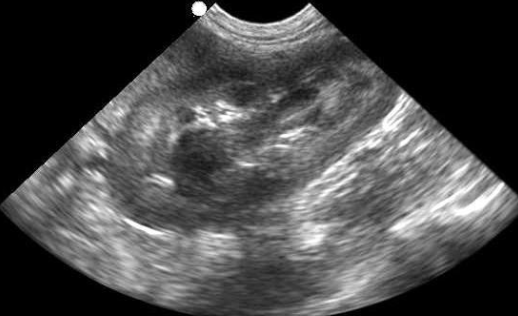

Abdominal ultrasound is a non-invasive, pain-free imaging tool that allows our veterinarians to see inside your pet’s abdomen in real time — helping us assess organs such as the liver, kidneys, spleen, bladder, and intestines with incredible detail.